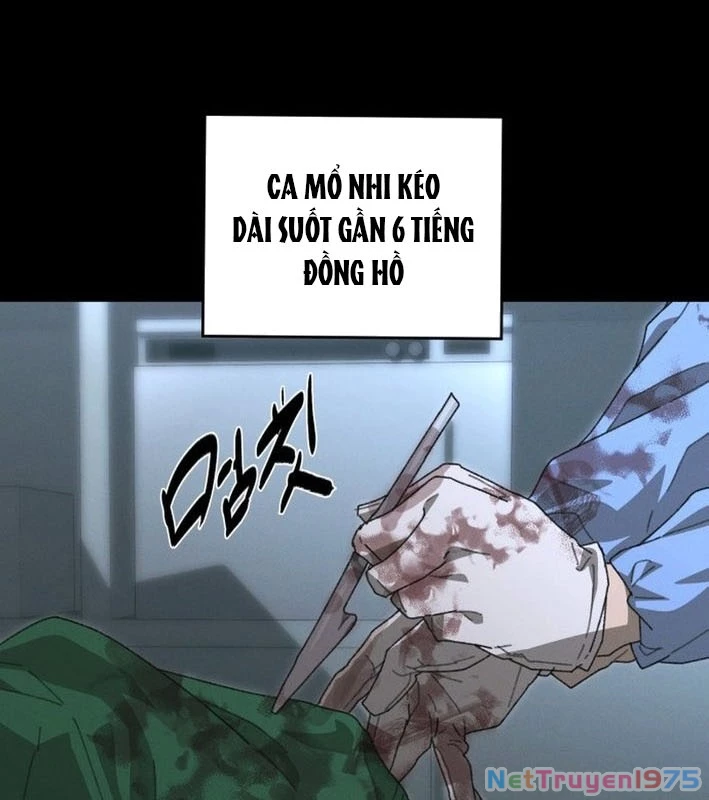

Kẻ Chôn Cất Quái Vật - Chapter 1